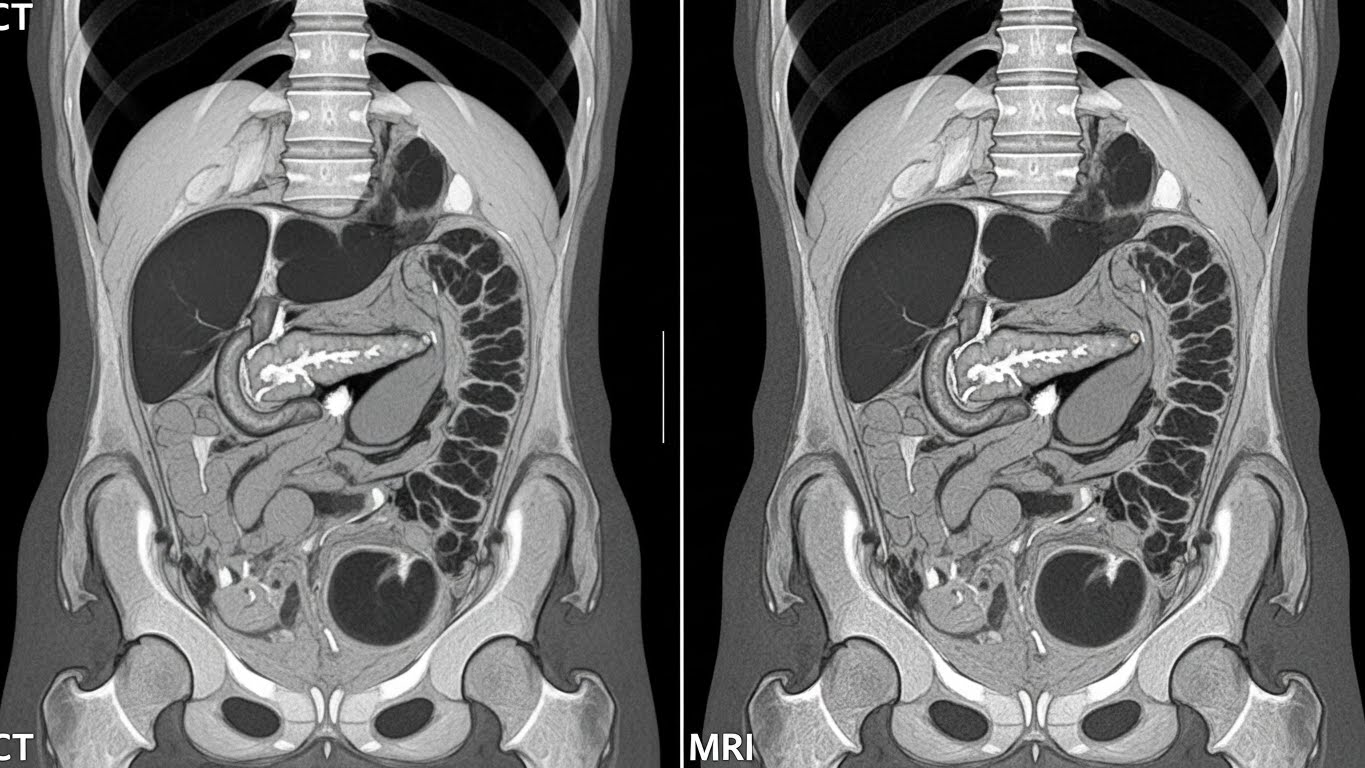

(2) 췌장암 정밀 검사의 핵심: CT vs MRI 비교

초음파에서 이상이 의심되거나 증상이 지속될 때 시행하는 정밀 검사가 바로 CT와 MRI입니다.

두 검사는 목적과 장점이 확연히 다릅니다.

신속하고 정확한 표준 검사, CT

다중시기 CT(Dynamic CT)는 현재 췌장암 진단과 병기 결정에 가장 널리 쓰이는 표준 검사입니다.

조영제를 주입해 췌장의 혈류 흐름을 시간차로 촬영하며, 암세포가 주변 혈관이나 장기로 침범했는지 판단하는 데 매우 탁월합니다.

검사 시간이 1~5분 내외로 짧아 응급 상황이나 숨을 오래 참기 힘든 고령자에게 유리합니다.

미세한 종양을 찾아내는 해결사, MRI

MRI(자기공명영상)는 CT에서 판별이 모호한 1cm 미만의 작은 종양이나 췌장관의 미세한 변화를 관찰하는 데 우수합니다.

특히 방사선 노출이 없고, 췌장액이 흐르는 통로를 입체적으로 보는 MRCP(자기공명담췌관조영술)를 통해

췌장 낭성 종양(물혹)이 암으로 변하는지 확인하는 데 최적화되어 있습니다.

다만, 검사 시간이 30분 이상으로 길고 비용이 높다는 단점이 있습니다.

최근에는 CT에서 확실치 않은 부분 보완하기 위해 MRI를 병행하는 '상호보완적' 방식을 많이 채택합니다.